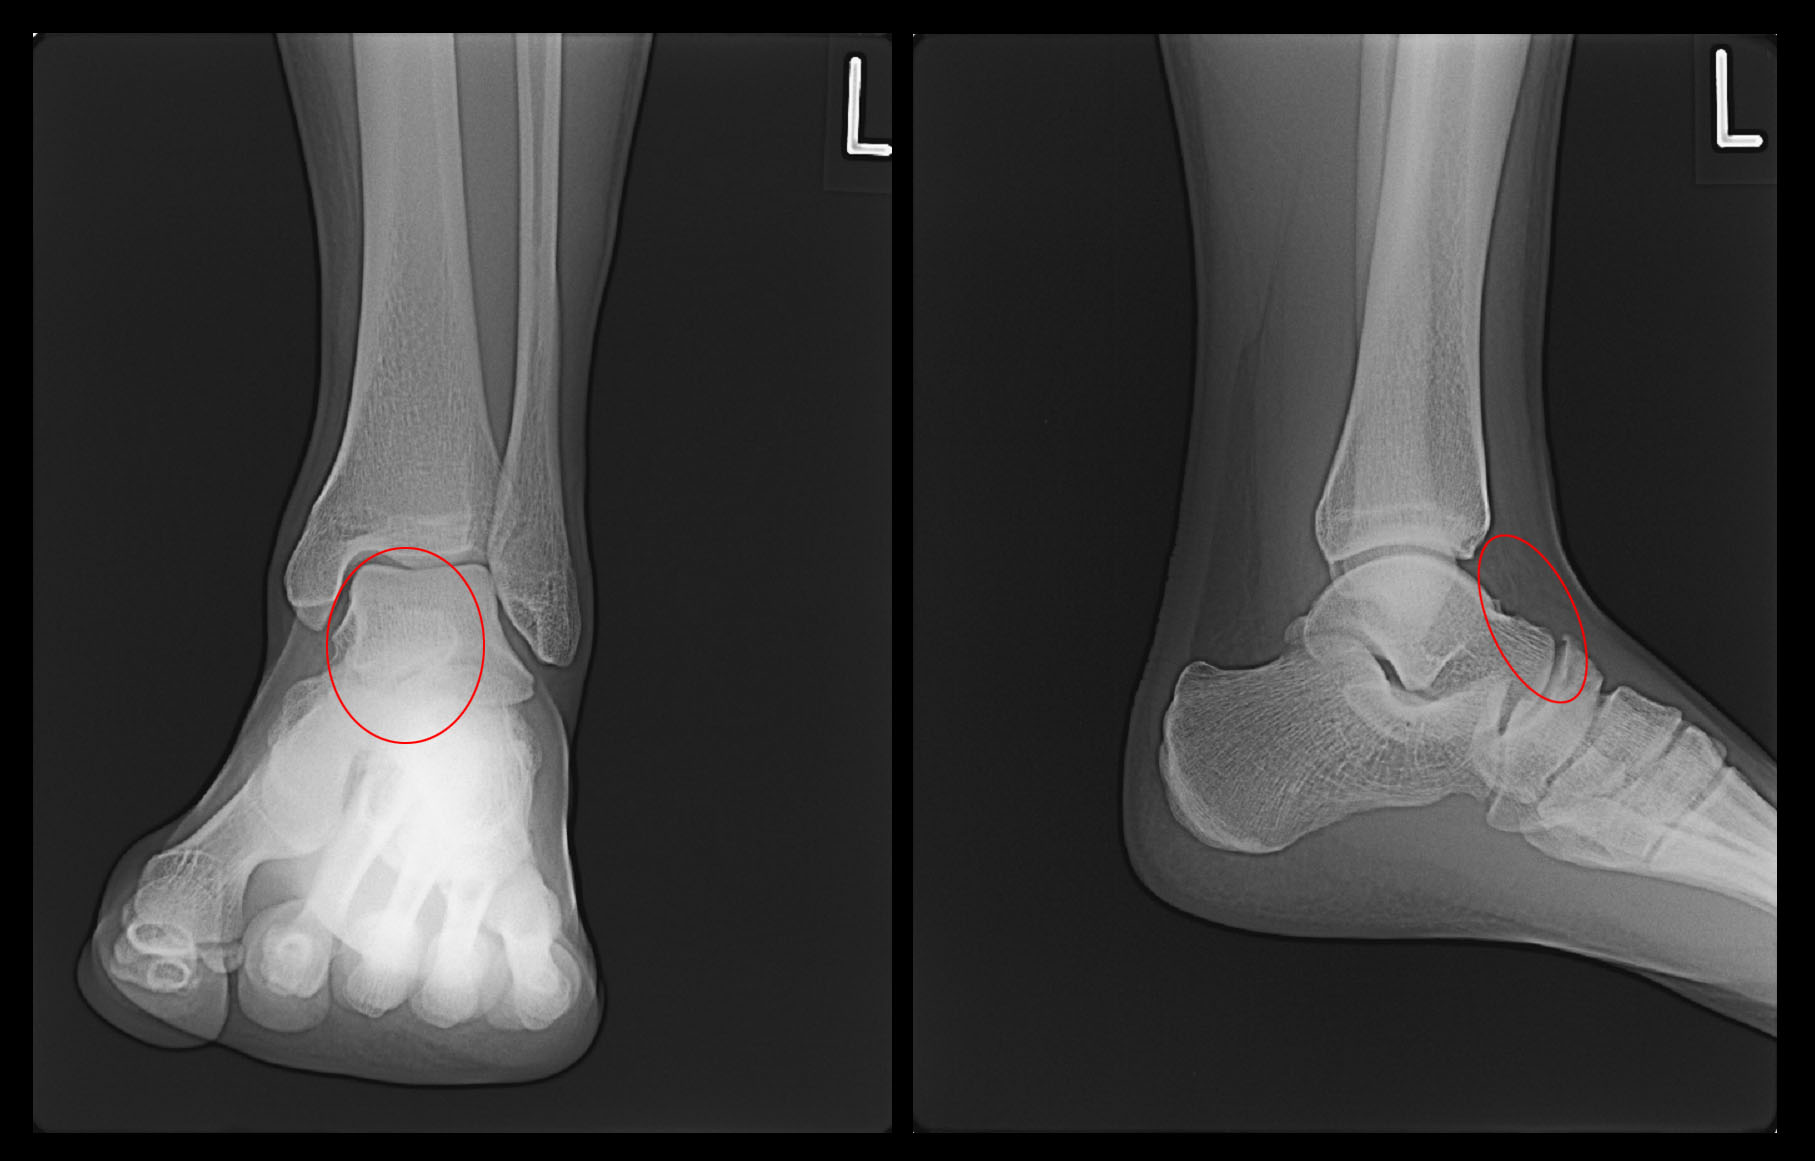

17才男性 高校2年生のサッカー部の選手です。平成24年7月14日に当院を受診されました。1か月前から左足関節の前方部に痛みを感じていたそうです。特に外傷があったわけではないと言っていました。7月14日の試合中に症状が悪化し、歩行も困難となり交代し、当院を受診されました。レントゲン像です。

赤丸が疼痛部位となりますが、特に腫脹はみられませんでした。